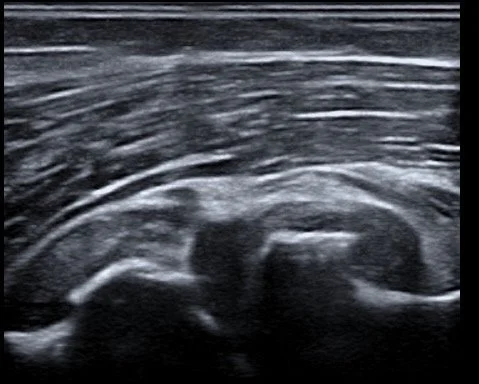

Imagen de una ecografía en blanco y negro mostrando un embarazo en desarrollo.

Un diagnóstico adecuado del dolor de codo comienza con una historia clínica detallada, que permite identificar cualquier lesión o movimiento repetitivo que pueda haber generado tensión en la articulación. Se realiza un examen físico exhaustivo para evaluar las zonas más dolorosas, comprobar el rango de movimiento y la fuerza, así como la presencia de inflamación. El Dr. Castillo utiliza ultrasonido durante la consulta para detectar inflamación o desgarros en los tendones y ligamentos, así como signos de artrosis en el codo. En algunos casos, pueden requerirse otras imágenes, como radiografías o resonancias magnéticas, para obtener una visión complementaria de las estructuras internas del codo. Una vez identificada la causa, se desarrollará un plan de tratamiento integral, adaptado a su condición específica.

Todas las inyecciones de PRP o Proloterapia se realizan bajo GUIA ECOGRAFICA lo que permite una mayor precisión al colocar el tratamiento directamente en el sitio de la lesión que origina el dolor.